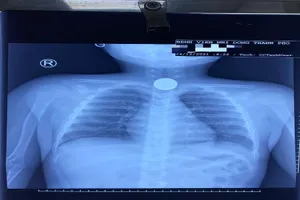

20 năm ho ra máu, mủ vì mảnh xương heo to bị bỏ quên trong phổi

Không ai quan sát, bé trai tự làm điều này mà không biết sẽ nguy hiểm